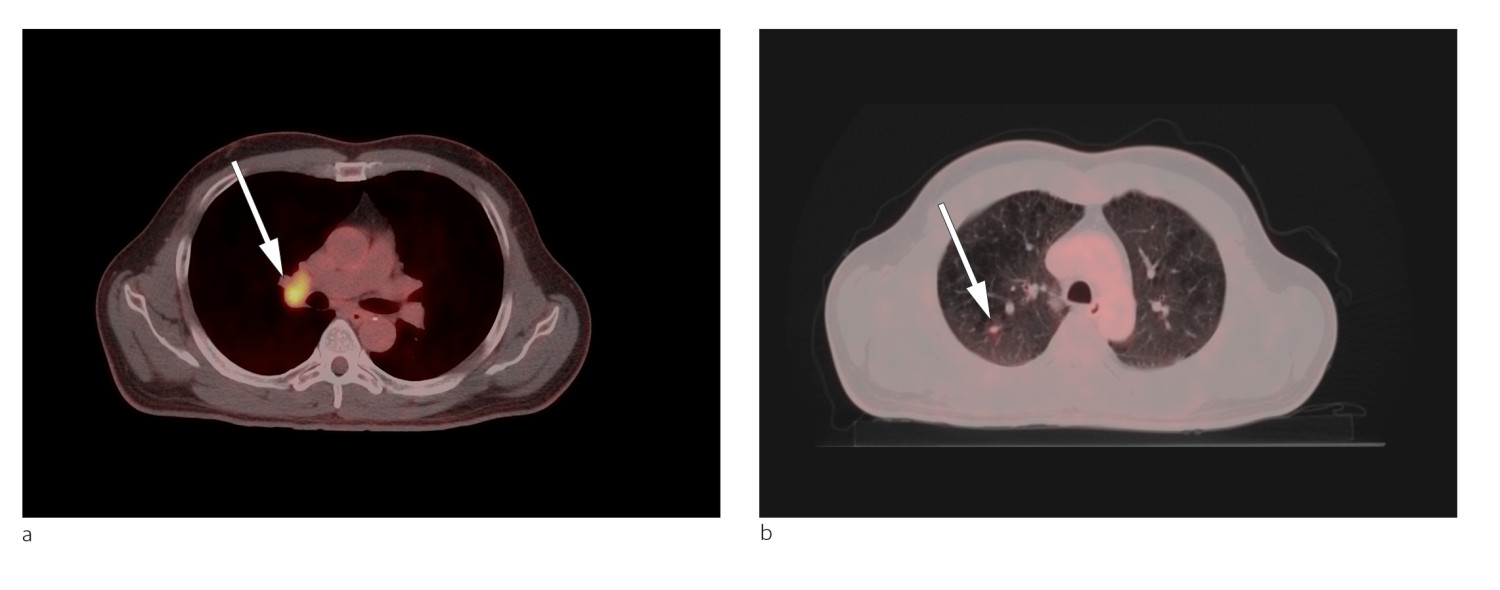

CT thorax viste uspesifikke små nodulære fortetninger i høyre lunge, den største med diameter 7 mm.

Lungekreft ble ikke påvist på CT thorax, men PET/CT helkropp viste malignitetssuspekte forandringer i høyre lungelapp og høyre hilus (fig 1). Cytologiske funn og biopsifunn fra lymfeknute i mediastinum bekreftet mistanken om småcellet lungekreft. Pasientens tilstand var forenlig med Lambert-Eatons myastenisk syndrom forårsaket av småcellet lungekreft ledsaget av cerebellær degenerasjon.